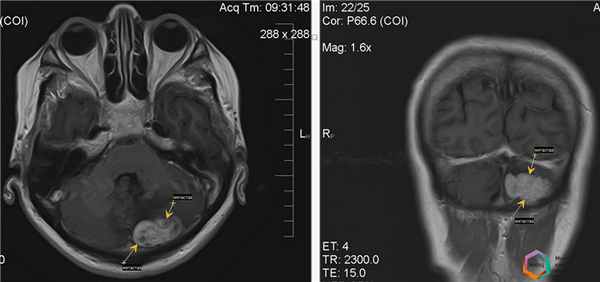

Клинический пример №2

Пациентка К., 61 года, обратилась в кабинет магнитно-резонансной томографии по поводу исследования головного мозга, беспокоят головные боли.

В анамнезе рак молочной железы, операция по поводу удаления образования не проведена, идёт диагностический поиск метастатического поражения других органов.

При проведении магнитно-резонансной томографии в различных режимах и трёх проекциях с применением внутривенного контрастного усиления выявлено множественное метастатическое поражение головного мозга с наличием зон перифокального отёка.

Помимо метастазов очевидных при нативном (бесконтрастном) сканировании, при внутривенном контрастном усилении выявляются дополнительные очаги метастатического поражения головного мозга более малых размеров, не визуализируемых ранее.